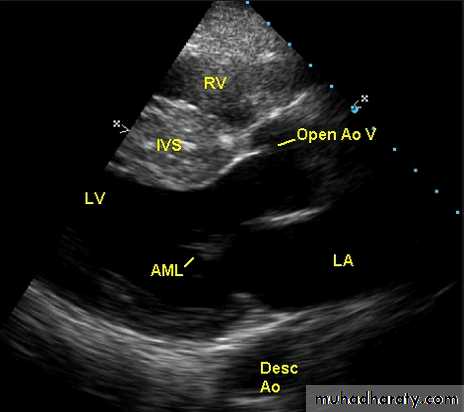

Echocardiogram: Chamber enlargement and global hypokinesisCXR

ECHO Echocardiography is diagnostic